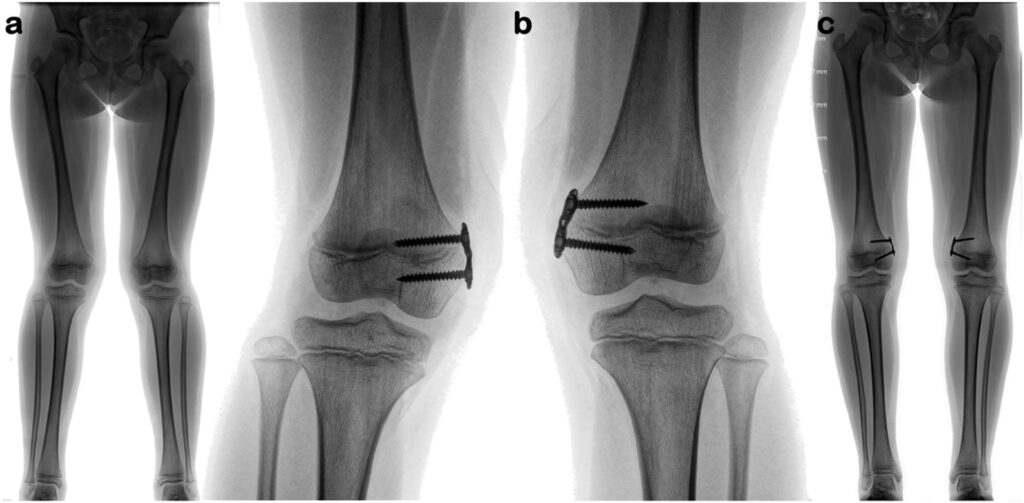

Para comprender la importancia clínica de la fisis y sus lesiones, es útil considerar un caso de genu recurvatum adquirido, una alteración angular del eje mecánico de la rodilla en su plano sagital, definida como un ángulo superior a 15° que requiere tratamiento quirúrgico. Si bien puede ser congénito, los casos adquiridos tienen diversas etiologías, incluyendo traumatismos, tracción transesquelética, intervenciones quirúrgicas cercanas a la fisis tibial proximal, enfermedad de Osgood-Schlatter, osteomielitis o inmovilización prolongada.

Se ha documentado el caso de un paciente varón de 15 años que, un año después de sufrir un traumatismo en el tobillo izquierdo (una epifisiolisis tipo II de Salter y Harris no desplazada en la tibia distal, tratada ortopédicamente con éxito), desarrolló gonalgia, limitación funcional y una deformidad de la rodilla izquierda en genu recurvatum. Las radiografías y una resonancia magnética revelaron un genu recurvatum óseo de 25° y un cierre fisario anterior de la tibia proximal izquierda, con la fisis prácticamente cerrada en comparación con la rodilla contralateral. Esto indicaba una epifisiodesis (cierre prematuro de la fisis) de la tibia proximal.

El paciente fue sometido a tratamiento quirúrgico, consistente en una osteotomía supratuberositaria tibial con una cuña ósea de adición de homoinjerto, que permitió restaurar la altura de la meseta tibial y elevar la rótula. Este caso subraya cómo una agresión a la fisis, incluso en una zona distante (tobillo) o de origen desconocido, puede tener repercusiones significativas en el crecimiento y la alineación de otras articulaciones, destacando la necesidad de una valoración exhaustiva por parte del especialista.